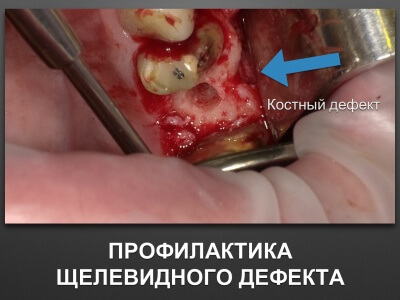

"Выстраданные" наборы инструментов

Все ниже перечисленные инструменты можно приобрести на сайте kohlermed.ru или связаться с нашим менеджером по тел 499-5179401

Все ниже перечисленные инструменты можно приобрести на сайте kohlermed.ru или связаться с нашим менеджером по тел 499-5179401